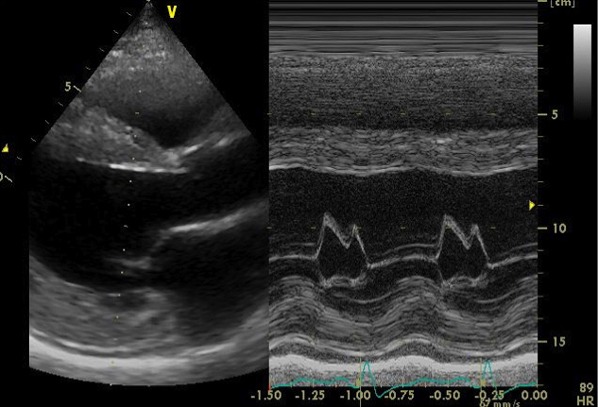

心エコー検査では、弁機能に異常なく、心嚢液の貯留はない。左房径(64mm)と左室径(60mm)は著明に拡張、左室は瀰漫性に壁運動の低下(EF=20%)。左室壁は中隔厚(18mm )、左室後壁厚(21mm)と共に肥厚しており、長年の左室圧負荷に加え、左室の収縮不全を認めることから、高血圧性心疾患に加え何らかの心筋疾患の可能性も否定できない。

心エコー画像2